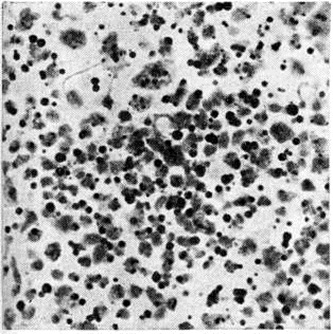

Острый миелобластный лейкоз в развёрнутой стадии болезни характеризуется выраженной лейкозной инфильтрацией костного мозга и других органов. В печени лейкозные разрастания локализуются в синусоидных капиллярах и в области портальных трактов. Аналогичное расположение инфильтратов имеется и при других более редких формах острого Лейкозы (монобластном, миеломонобластном, недифференцируемом, промиелоцитарном и другие), поэтому данный признак не может служить основанием для разграничения форм острого Лейкозы В лёгких лейкозная инфильтрация обычно выявляется по ходу межальвеолярных перегородок с выходом бластных клеток в просветы альвеол (рисунок 3), возможна локализация и в окружности бронхов, сосудов, междольковых перегородках. У детей при этой форме Лейкозы лейкозные разрастания в вилочковой железе располагаются в соединительнотканных прослойках, сдавливают дольки, что сопровождается увеличением количества аргирофильных волокон. У взрослых типично развитие множественных узлов в надкостнице плоских и трубчатых костей, почках, печени, половых железах, жировой клетчатке (подкожной, ретробульбарной, клетчатке большого сальника и малого таза), иногда в коже, конъюнктиве, твёрдой мозговой оболочке и костном мозге. В ряде случаев в области опухолевых узлов и системных поражений имеется зелёное окрашивание ткани (хлоролейкоз). Аналогичные изменения могут выявляться и при Лейкозы у детей.